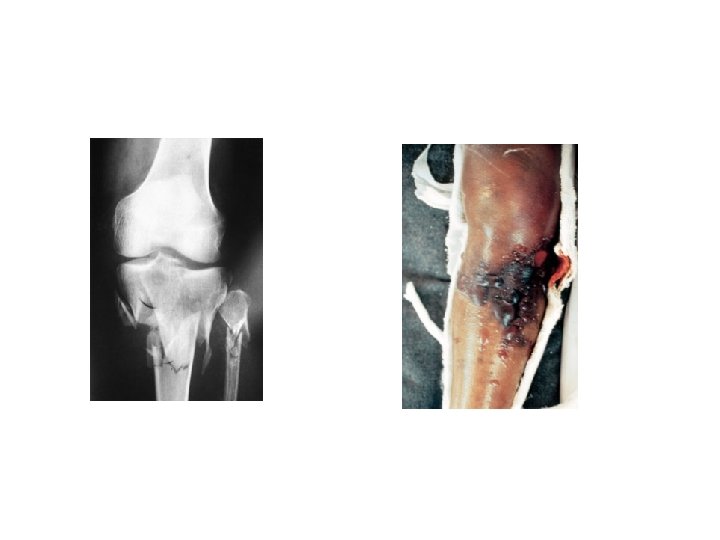

2 -VASCULAR INJURY The fractures most often associated with damage to a major artery are those around the knee and elbow, and those of the humeral and femoral shafts. The artery may be cut, torn, compressed or contused, either by the initial injury or subsequently by jagged bone fragments. The effects vary from transient diminution of blood flow to profound ischaemia, tissue death and peripheral gangrene.

• Clinical features The patient may complain of paraesthesia or numbnessin the toes or the fingers. The injured limb is cold and pale, or slightly cyanosed, and the pulse is weak or absent. X-rays will probably show one of the ‘highrisk’fractures listed above. If a vascular injury is suspected an angiogram should be performed immediately; if it is positive, emergency treatment must be started without further delay. • Treatment All bandages and splints should be removed. The fracture is re-x-rayed and, if the position of the bones suggests that the artery is being compressed or kinked, prompt reduction is necessary. The circulation is then reassessed repeatedly over the next half hour. If there is no improvement, the vessels must be explored by operation preferably with the benefit of preoperative or peroperative angiography. A cut vessel can be sutured, or a segment may be replaced by a vein graft; if it is thrombosed, endarterectomy may restore the blood flow. If vessel repair is undertaken, stable fixation is a must and where it is practicable, the fracture should be fixed internally.

4 - COMPARTMENT SYNDROME Fractures of the arm or leg can give rise to severe ischaemia, even if there is no damage to a major vessel. Bleeding, oedema or inflammation (infection) may increase the pressure within one of the osseofascial compartments; there is reduced capillary flow, which results in muscle ischaemia, further oedema, still greater pressure and yet more profound ischaemia a vicious circle that ends, after 12 hours or less, in necrosis of nerve and muscle within the compartment. Nerve is capable of regeneration but muscle, once infarcted, can never recover and is replaced by inelastic fibrous tissue (Volkmann’s ischaemic contracture). A similar cascade of events may be caused by swelling of a limb inside a tight plaster cast.

Treatment The threatened compartment (or compartments) must be promptly decompressed. Casts, bandages and dressings must be completely removed – merely splitting the plaster is utterly useless – and the limb should be nursed flat (elevating the limb causes a further decrease in end capillary pressure and aggravates the muscle ischaemia). The ΔP should be carefully monitored; if it falls below 30 mm. Hg, immediate open fasciotomy is performed. In the case of the leg, ‘fasciotomy’ means opening all four compartments through medial and lateral incisions. The wounds should be left open and inspected 2 days later: